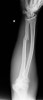

X-ray : 야경봉 골절(Night stick fracture)

다른 전완부 골절과 마찬가지로 X-ray 촬영시 주관절로 완관절을 포함합니다.

X-ray만으로도 쉽게 진단할 수 있습니다.